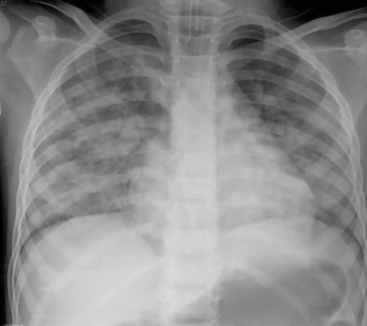

Left atrial enlargement may be difficult to discern on a chest radiograph, because the left atrium normally does not form a distinct portion of the cardiac margin. With left atrial enlargement, the left heart border below the aortic knob may straighten or become convex instead of concave. In addition, the posterior enlargement of this chamber can elevate the left mainstem bronchus so that the angle of the tracheobronchial bifurcation is widened. A double density also may be observed in the center of the cardiac shadow14,21 (Fig. 10-13).

image

Fig. 10-13 Congestive heart failure with pulmonary edema. This 5-year-old boy with known mitral insufficiency was admitted to the critical care unit with tachypnea and increased respiratory effort. On physical examination, he demonstrated a heart rate of 137/min with a gallop rhythm. The respiratory rate was 54/min with moderate retractions. Breath sounds were adequate and equal bilaterally, and crackles were noted, particularly over the left lung fields. The child’s liver was palpable 6   cm below the right costal margin. The child also had cardiomegaly (cardiothoracic ratio of 0.6). The double density seen within the heart (large arrows) is caused by the large left atrium. Pulmonary interstitial markings are prominent and hazy through both lung fields. Kerley B lines are noted in the base of the right lung (small arrows).

(Courtesy Andrew K. Poznanski, Children’s Memorial Hospital, Chicago, IL.)

Cardiac enlargement often is seen when the child has congestive heart failure. Heart failure, often biventricular in children, can produce a global enlargement of all heart chambers.14 Pulmonary vascular markings also will be indistinct (see Fig. 10-13).